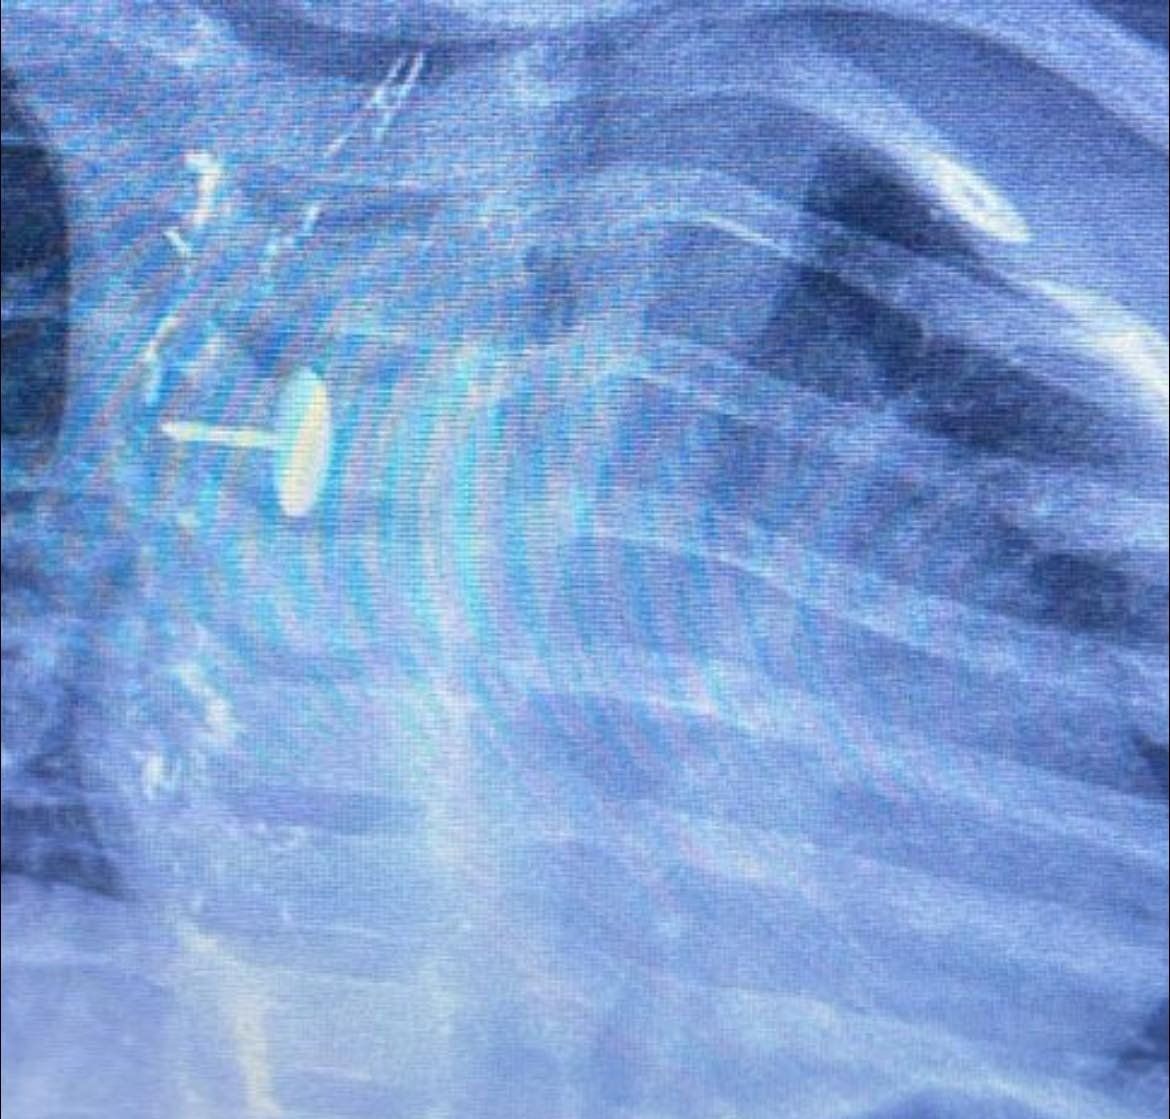

نجح فريق قسم جراحة الأطفال، بمستشفى الأطفال التخصصي ببنها، بمحافظة القليوبية، بقيادة الدكتور محمد متولي رئيس قسم جراحة الأطفال، في إجراء عملية دقيقة لاستخراج دبوس ضغط من مريء طفلة عمرها سنة و7 أشهر، كانت قد ابتلعته منذ 6 أشهر.

الجسم الغريب استقر داخل جدار المرئ

كشفت مستشفى الأطفال التخصصي ببنها، في بيان لها، أن الجسم الغريب استقر داخل جدار المريء، مما تسبب في عدم قدرة الطفلة على البلع طوال هذه الفترة، وجعل حياتها في خطر دائم. استخدام أحدث الأجهزة في الجراحة

دبوس ضغط فى مرئ طفلة